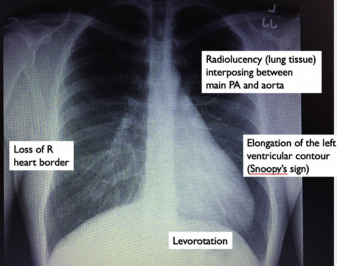

CXR

• Left CPA heart can shift posterior and left causing straightening and elongation of heart (levorotation and levoposition)

• "Snoopy" Sign

Case 1

ECG: incomplete RBBB, poor R wave progression, right axis deviation

29M presented with atypical chest pain